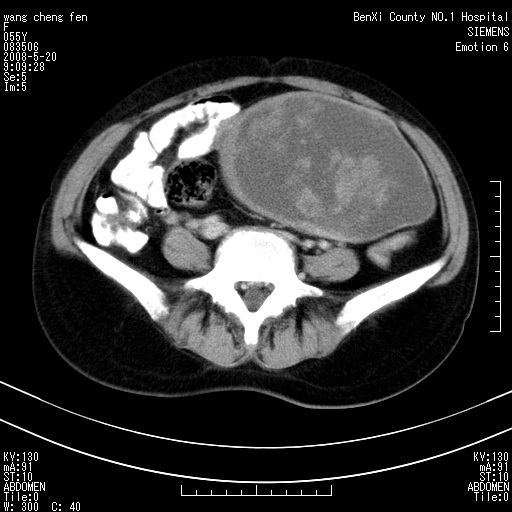

女、绝经后阴道流血3个月

左侧附件区可见一囊性占位,边缘清楚,内可见不规则形软组织影 ce:囊壁及内部可见强化 考虑 卵巢囊腺瘤

左侧附件区巨大囊实性病灶,边缘光整,病灶囊壁较厚,增强示囊壁及实性部分明显强化,强化呈度与宫体实质大致相同,宫腔积液征像,未见盆腔积液等其他异常,考虑左侧卵巢囊腺癌,不除外囊腺瘤及浆膜下肌瘤坏死

左侧附件区巨大囊实性病灶,边缘光整,病灶囊壁较厚,增强示囊壁及实性部分明显强化,强化呈度与宫体实质大致相同,宫腔积液征像,未见盆腔积液等其他异常。绝经后阴道流血3个月,结合病史左侧卵巢囊腺癌首先考虑,宫腔扩大不除外累及。期待结果。

囊实性肿块分隔厚度较大,厚薄不均,增强实性成分明显强化,有不规则阴道流血,卵巢囊腺癌可能性大。